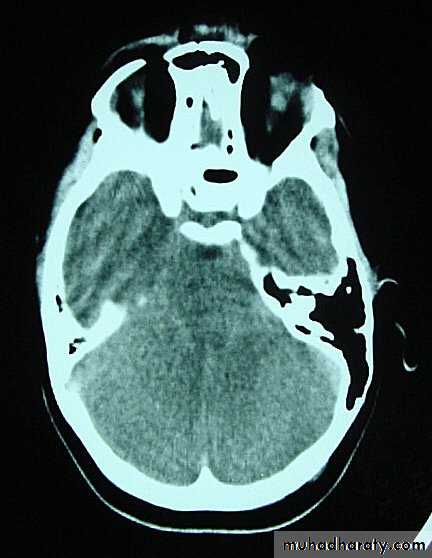

d. Subarachnoid Haemorrhage

Trauma is the commonest cause of SAH although aneurysms are the most common cause of spontaneous SAH.

Traumatic SAH is managed conservatively.